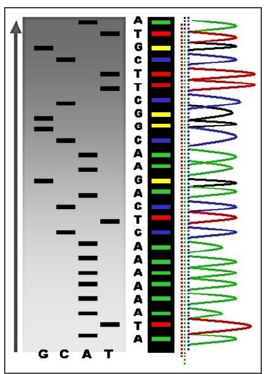

To really understand PPM and PPO we would have to understand the various fields of translational applications that provide the tools to exploit and practice PPM, and genomics tools, in particular! (Figure 3A, B) and are two techniques in Personalized Genomics technologies-related portfolio. Generally, they provide information about the genome of an individual.

Basically, DNA profiling is the technique, or even approach, widely applicable in PPM- and PPO-related genomic testing for the identification of individuals depending on their genetic makeup [4].

The main difference between DNA profiling and DNA sequencing is their procedure and clinical importance (Figure 4). The human genome holds the clues to diverse diseases and improved quality of life. Pro-vocatively, one can raise a question whether in the genome resides a signature for healthy dis-ease-free life? What would it take to approach wellness of human beings from a health rather than disease perspective? So, Genomics is a set of the unique biomarkers and thus the molecular tools to probe genome for its quality and now even be tested to secure genome profiling (see above).

Genomics probes the general principles of the functional

architecture of genomes. So, genetic testing can provide information

about person’s genes, their products, and chromosomes [5]. And

thus, for screening and monitoring the human health, family future

and the healthy stability of the nation, a set of testing platforms has

been translated into the daily common and cancer-related practice

to secure the fastest development of the technologies to include:

a. Genome se-quenching and

b. Nucleotide polymorphism testing (Figure 5).

Currently, particular attention is being paid to the development of pathological genomics, which allows not only for molecular genetic diagnostics, but is also an important step to deter-mining the intensity of RNA transcription and protein translation in relation to the onset and development of diseases. A clear example of promising developments in this field are results from translational genomics crystallized into DTC-testing aimed at precise and reliable diagnosis that can inform the implementation of disease preventive strategies and preventative manipulations.